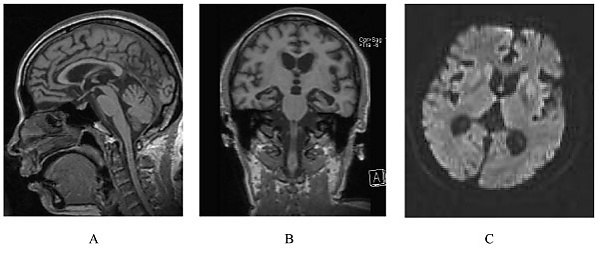

При проведении магнитно-резонансной томографии головного мозга у некоторых пациентов с СГШШ могут выявляться типичные нейровизуализационные признаки. К таким признакам относится гиперинтенсивность базальных ядер, таламусов и в некоторых случаях коры больших полушарий в режиме Т2-FLAIR и на диффузионно-взвешенных изображениях. Однако в большинстве случаев по мере прогрессирования заболевания обнаруживаются лишь неспецифические атрофические изменения головного мозга[4].